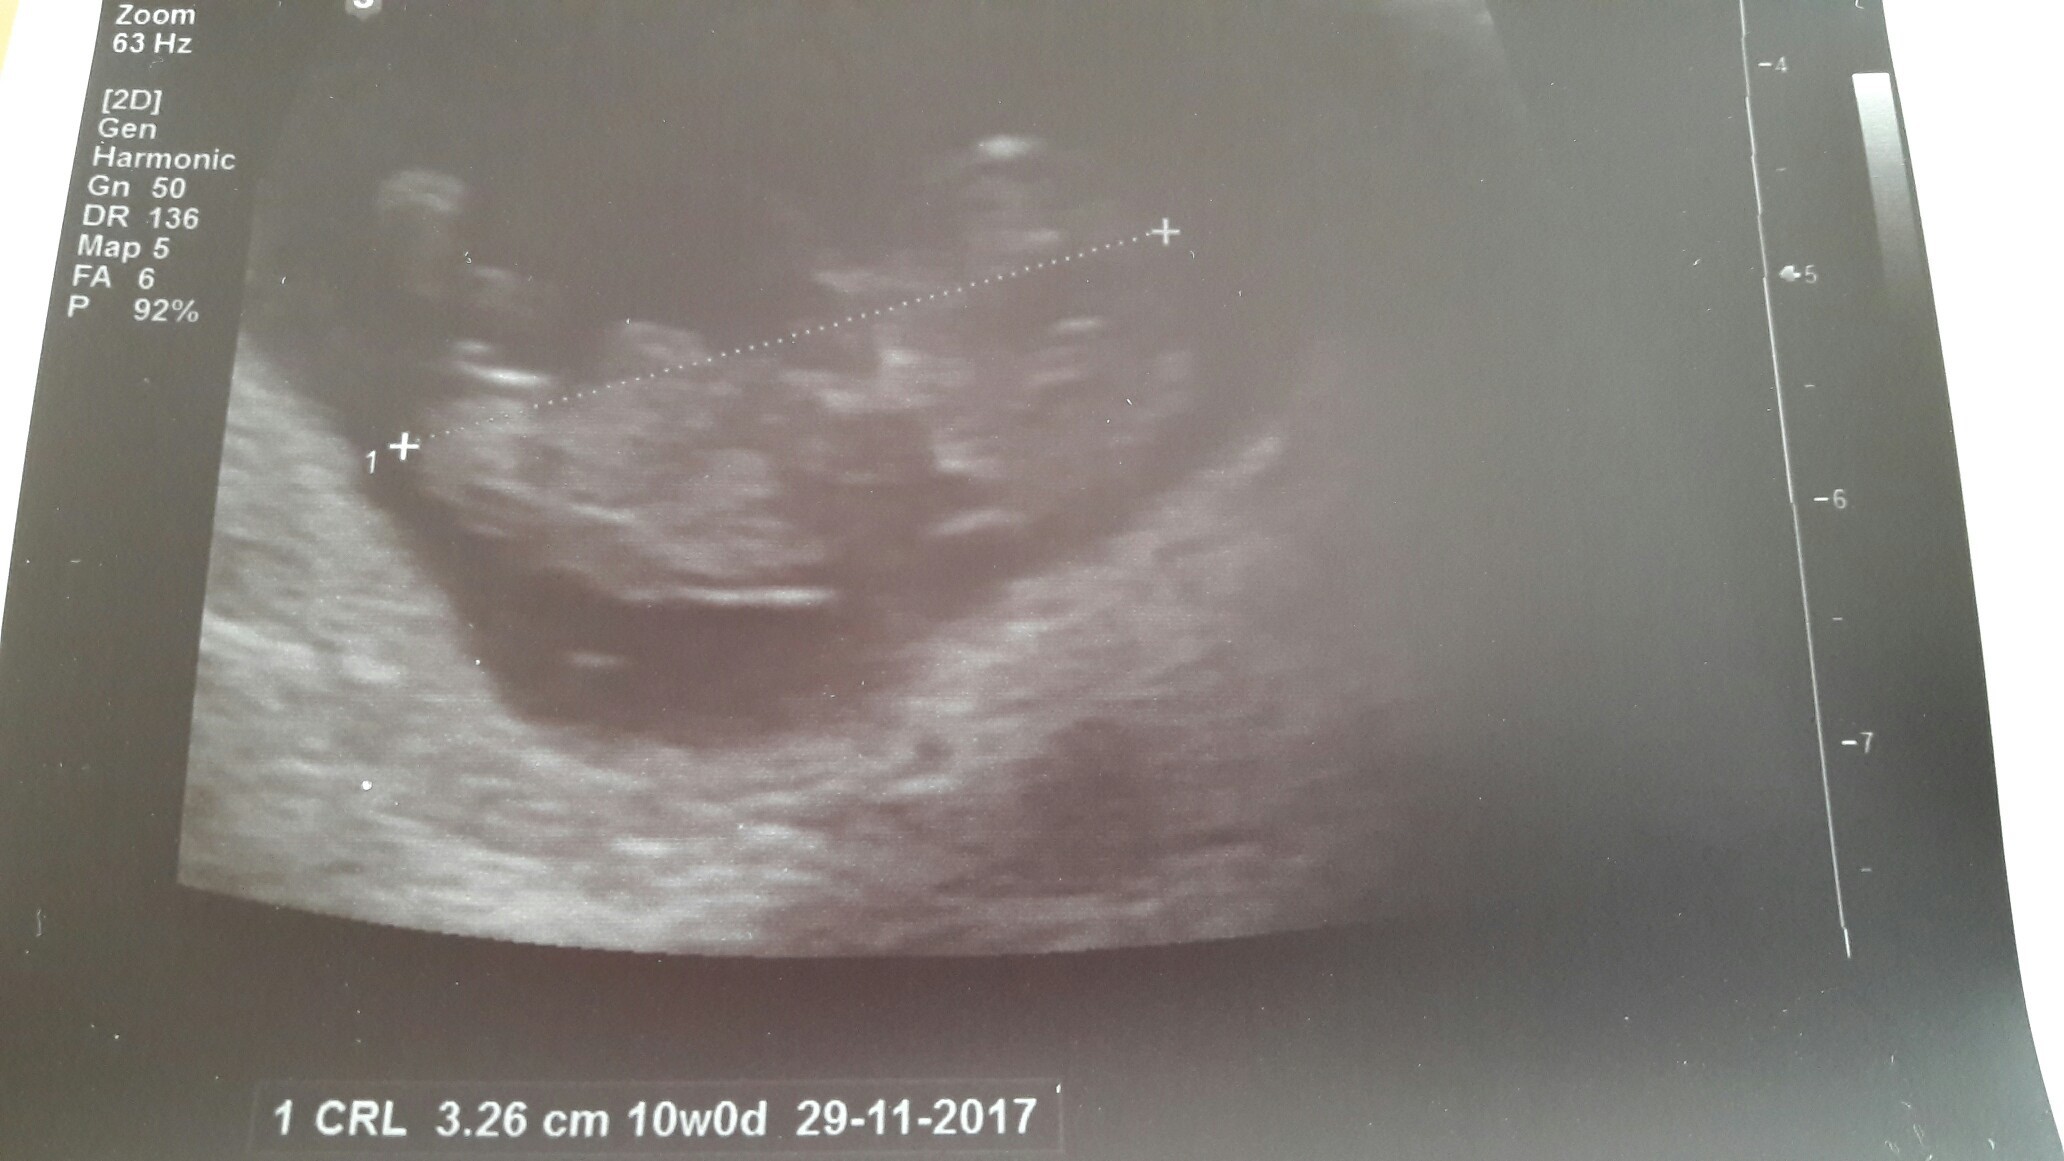

Ja już po wizycie. Krwiaka brak! Ale nikt zbytnio się nad tym nie skupiał, bo zobaczyłam tego oto małego czlowieczka. Machał do mnie rączką! Serce jak dzwon. Wielkość dzidziusia 3,25. I znowu z usg wychodzi mi termin jak z Om, choć ostatnio wyliczył, że dziś byłby 9t4d. Na usg zobaczyłam dziś 10 t0d. Ale wiadomo dwa dni w tą czy w tamtą nie mają znaczenia.

Bardzo się dziś wzruszyłam. Dzidziuś pokonał krwiaka.. A ja zaliczyłam pierwsze usg przez brzuch! Wow